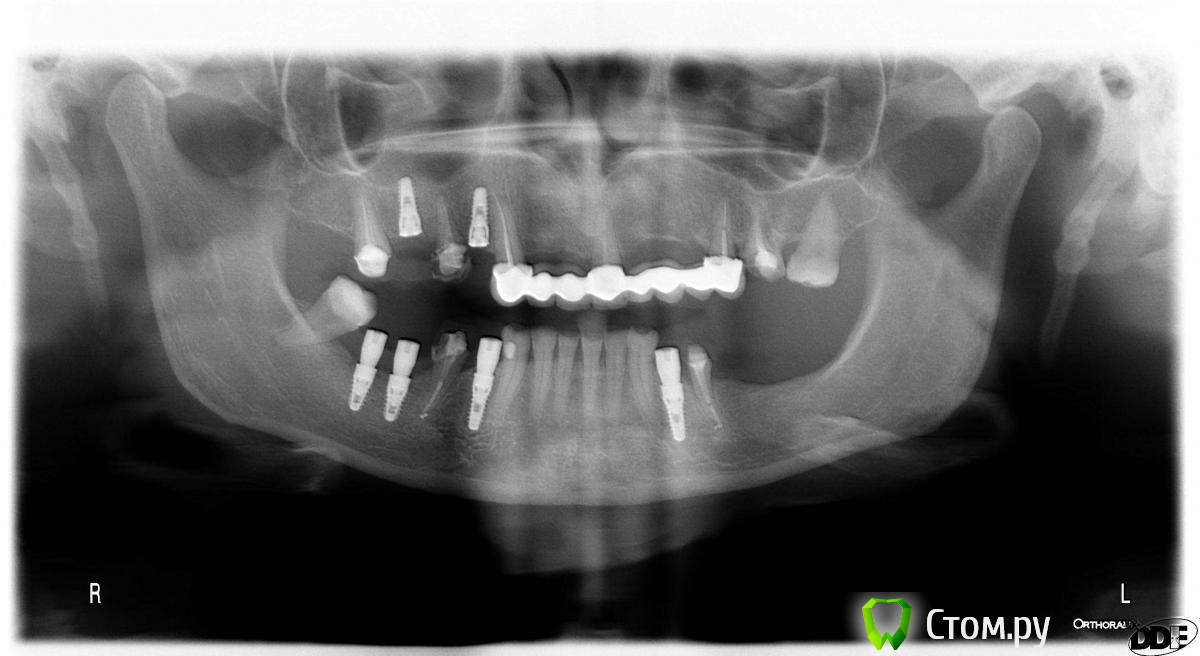

Евгений Ходыкин Опубликовано 2 июля, 2014 Автор Поделиться Опубликовано 2 июля, 2014 После имплантов дальше что планируете в боковых отделах??Дистальные отделы уже заимплантированы, если это имели ввиду. Ссылка на комментарий

4ebstom Опубликовано 2 июля, 2014 Поделиться Опубликовано 2 июля, 2014 Кт до вмешательства значит.Понял спс)) Ссылка на комментарий

Евгений Ходыкин Опубликовано 11 июля, 2014 Автор Поделиться Опубликовано 11 июля, 2014 Сегодня поставил. Действительно ограничился 3.8Х10. Спасибо всем, кто участвовал 4 Ссылка на комментарий